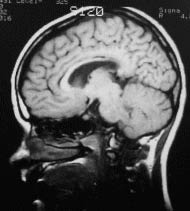

ANAMNESE

PEDAGÓGICA